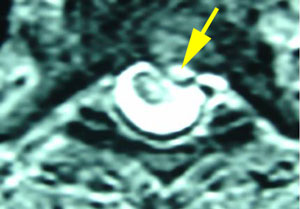

Figure 4 shows an MRI image of a cervical spine disc herniation from the top (See arrow.) as it moves backward and contacts the spinal cord which is implicated as a cause of headache.